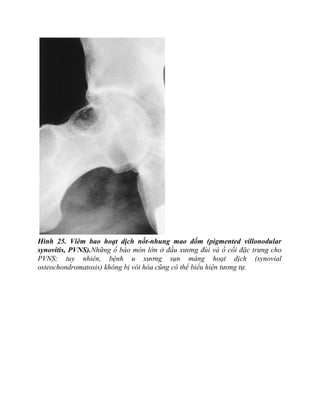

Hình 25. Viêm bao hoạt dịch nốt-nhung mao đốm (pigmented villonodular

synovitis, PVNS).Những ổ bào mòn lớn ở đầu xương đùi và ổ cối đặc trưng cho

PVNS; tuy nhiên, bệnh u xương sụn màng hoạt dịch (synovial

osteochondromatosis) không bị vôi hóa cũng có thể biểu hiện tương tự.